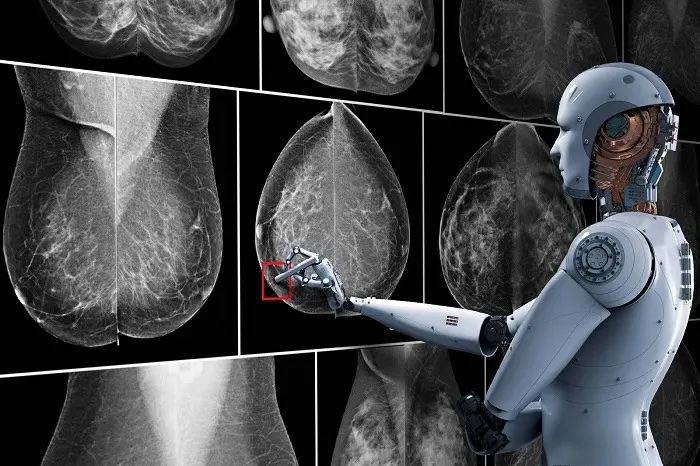

Einsatz von künstlicher Intelligenz

Hier kommt im Radiologischen Zentrum nun neuerdings künstliche Intelligenz zum Einsatz. Nach dem Motto "Vier Augen sehen mehr als zwei" werden die Aufnahmen auch von einer künstlichen Intelligenz beurteilt und dabei erkannte auffällige Befunde werden kenntlich gemacht. Letztlich entscheidet aber die Radiologin oder der Radiologe, die/der weitere Informationen aus der Vorgeschichte, den Tastbefund und die Ultraschalluntersuchung einbeziehen kann.

Wissenschaftliche Studien haben aber gezeigt, dass mit diesem Prinzip der KI-Zweitbefundung weniger krankhafte Befunde übersehen werden.

KI Software

Die von uns verwendete KI Software stammt von der Schweizer Firma b-rayZ AG. Sie wurde an tausenden von Mammographien mit gesicherten Befunden "angelernt" (Machine Learning). Die Software wird im Rahmen des Qualitätsprogramms QuaMaDi eingesetzt, kommt aber bei uns auch Patientinnen zugute, die nicht an QuaMaDi teilnehmen (können).